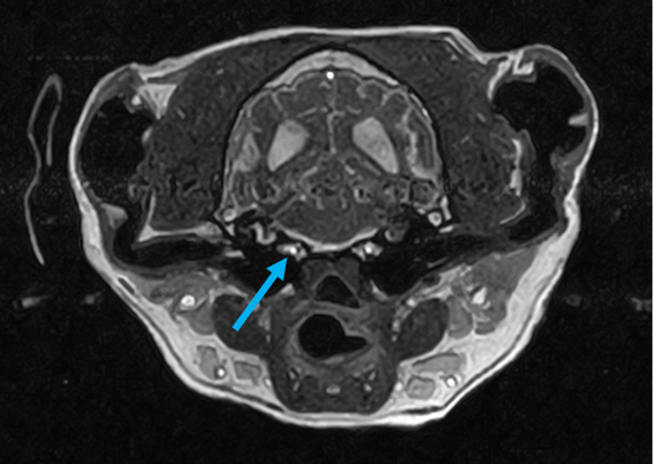

W obrębie mózgowia i trzewioczaszki najczęstszymi wskazaniami do badania MRI są:

• ocena patologii ucha zewnętrznego, środkowego oraz wewnętrznego

• patologie w obrębie oczodołów i struktur przyległych – ocena zmian pourazowych, zapalnych i nowotworowych

• zmiany zaoczodołowe i około zębowe – diagnostyka przewlekłych infekcji